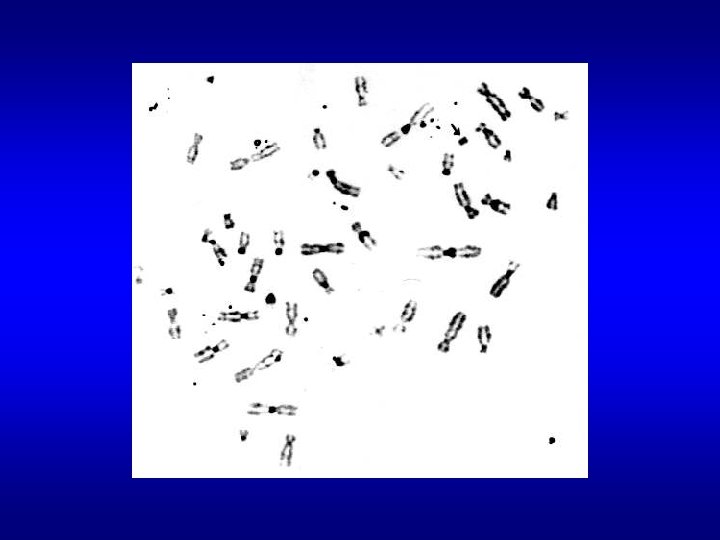

ANOMALIE CROMOSOMICHE